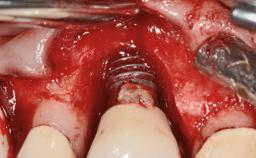

Management of a Fractured Implant Supporting a Screw-retained Metal-ceramic Restoration

The fracture of an implant after it has been restored is one of the most severe complications. It most frequently occurs in partially edentulous jaws (1.5%). Most implant fractures involve implants with a diameter of 3.75 mm made of commercially pure titanium (Eckert 2010). Unfortunately, many cases are not reported or documented by the clinicians involved in resolving the problems created by the fracture. This case report describes the management of an implant fracture at site 36 in a middle-aged male patient. The implant had been restored with a screw-retained metal-ceramic crown.